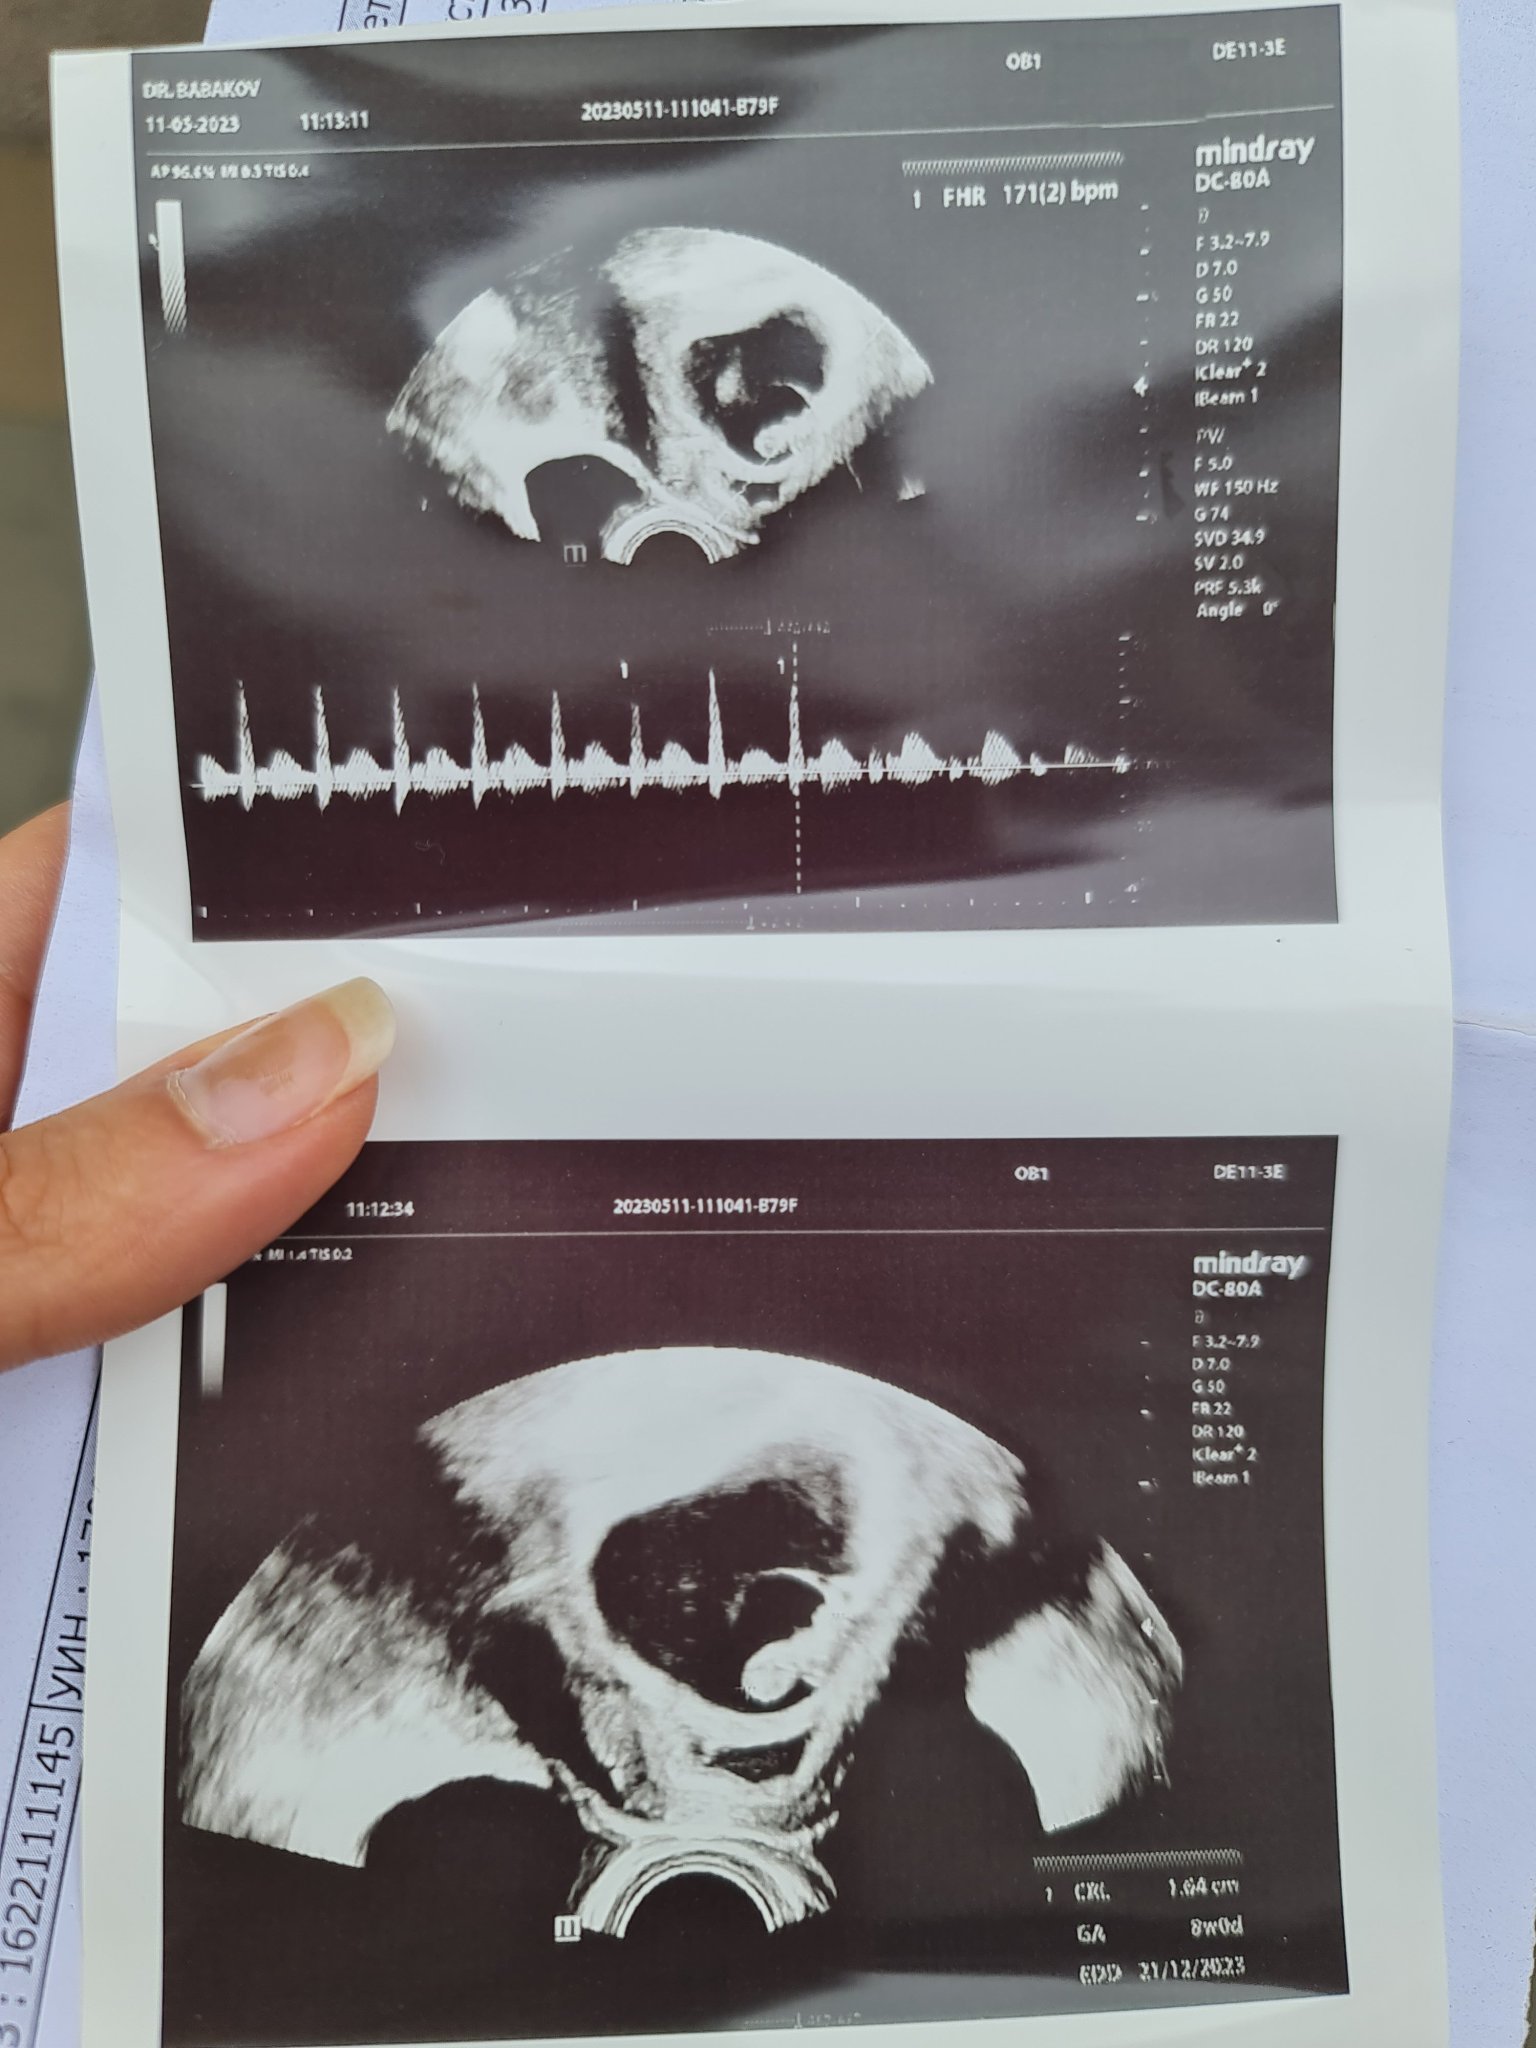

Момичета, и аз да се похваля с 1,6 см човече със силен здрав пулс. Пуснаха ми да чуя сърцето ❤️ Първата ни среща беше прекрасна и сякаш за първи път осъзнах какво се случва 🤣 Малкият фасулчо върви точно по график - по закъснение днес съм 8+2 седмици - на толкова и отговаря. Старнно календарите ми изчисляват дата 19.12 термин, но АГ ме записа 22.12. Както и да е, стана ясно откъде беше зацапвавето. Имам отлепяне на сака, съответно хематом, но докторът не каза да има нещо много притеснително и продължаваме 2х2 утрогестан и ограничаване на интимност. Не е споменавал лежане. Надявам се да съм го изчистила до следващия преглед, който ще е след 2 седмици. Пожелавам още много силни сърчица да бъдат чути!